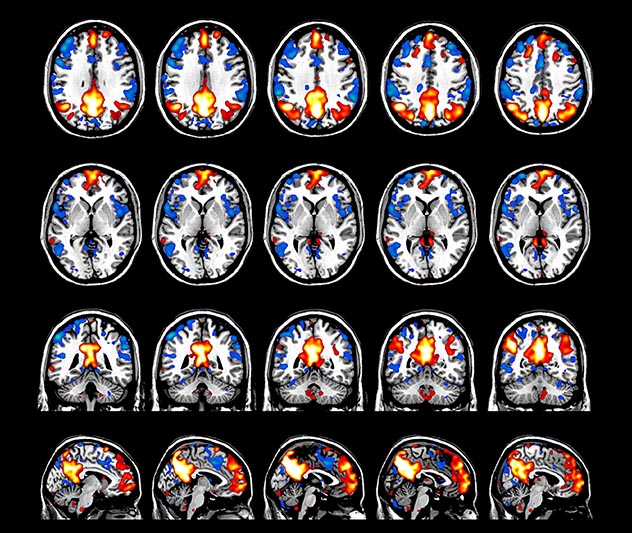

BOLD fMRI activation, depicted in color, of left anterior insula (MNI plane z = 8 mm) in a single subject by a contrast between viewing and matching faces with negative emotion (angry, sad, scared) versus happy faces. The voxelwise threshold is p < 0.001, and colored voxels survive false discovery rate correction to p < 0.05. The activated voxels in color are overlaid on the subject's own 3D-TFE image displayed in grayscale, after transforming the data to MNI space. The fMRI pulse sequence was a single shot FFE echo planar acquisition using MultiBand SENSE factor 6, dS SENSE factor 1, isotropic voxel size 2.4 mm, 60 transverse slices, TR 950 ms, TE 30 ms, flip angle 52 degrees, 517 dynamic scans, total scan duration 8:21 minutes. Image provided by James M. Bjork, PhD, Associate Professor of Psychiatry at VCU.

Emotional n-back task combines a test of working memory with the use of emotive (faces) and neutral (places) images. The contrast in the images is between the activity when faces are presented compared to places, showing activation in the amygdala, fusiform, and occipital face areas.

Processing based on the Human Connectome Project (HCP) pipelines. The high resolution of the fMRI data allows extraction of the cortical surface, with minimal averaging of non-cortical signal. Surface based analysis provides improved cross-subject alignment, and prevents signal contamination between adjacent sulci.

Group analysis of 88 9- and 10-year olds part of ABCD, all scanned at UVM on Philips Achieva 3.0T dStream. Scale runs from red p=0.001 to yellow p<10ˆ-5. Images provided by Dr. Watts.

Acquisition using the ABCD protocol for fMRI with TR 800 ms, TE 30 ms, flip angle 52°, 2.4 mm isotropic imaging resolution with a 216×216×144 mm3 field of view using a MultiBand acceleration factor of 6 (60 slices, no gap). Two runs of 5 minutes per subject.